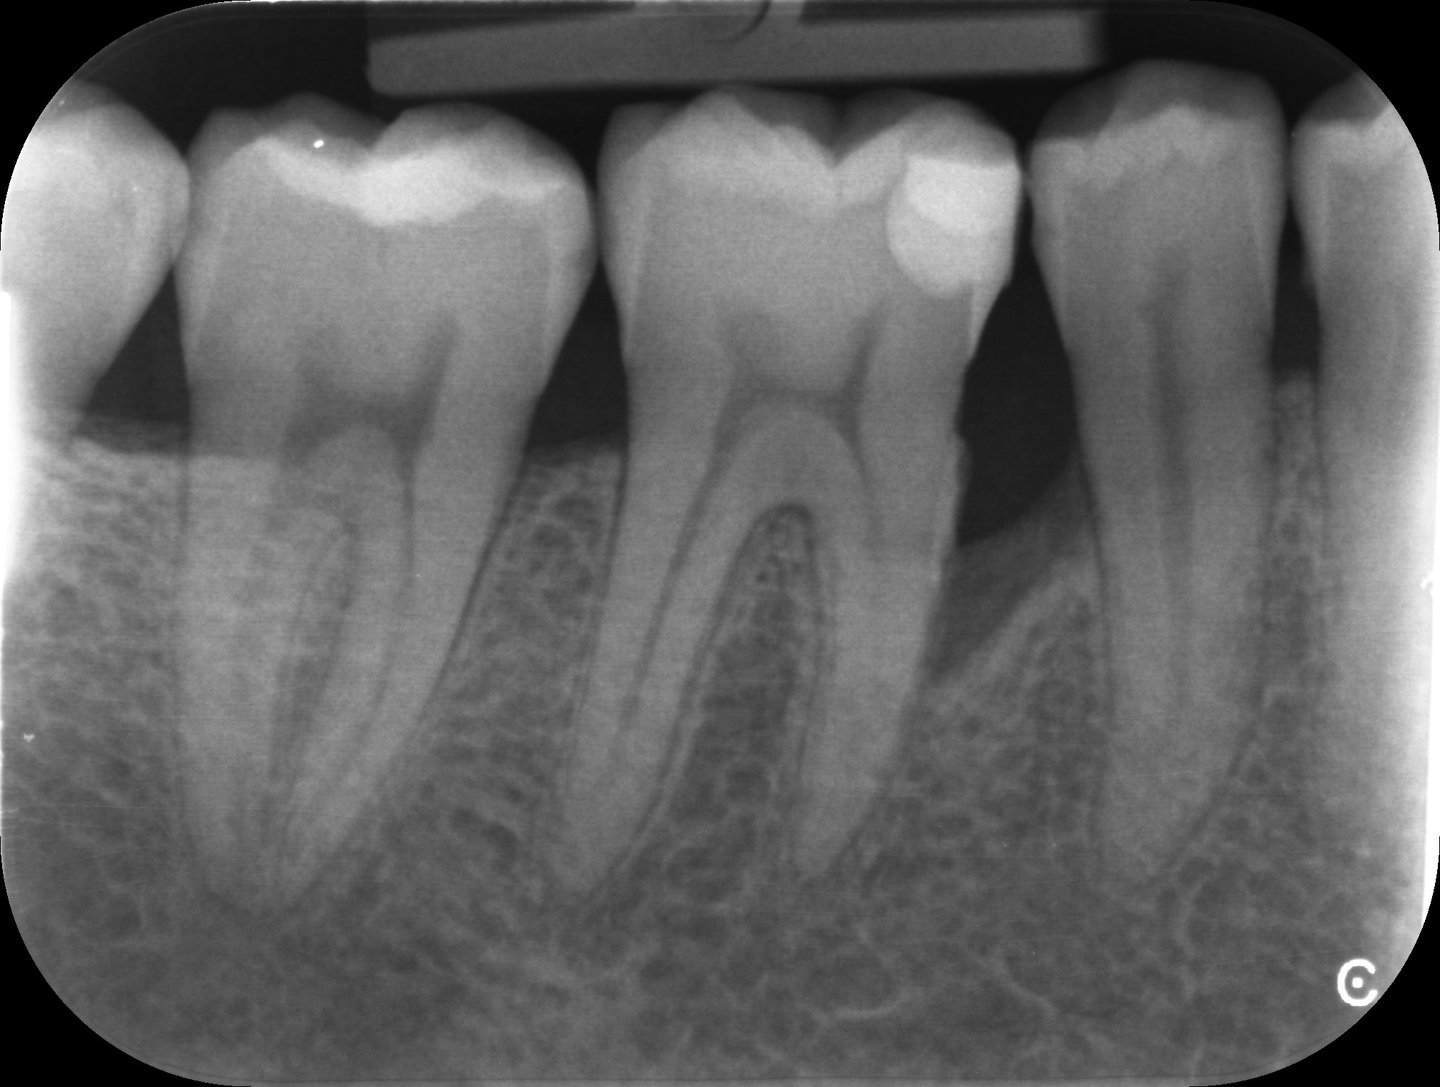

Grâce aux vignettes cliniques, vous découvrirez des situations et radiographies concrètes, vous permettant d’appliquer directement ces recommandations dans votre pratique quotidienne.